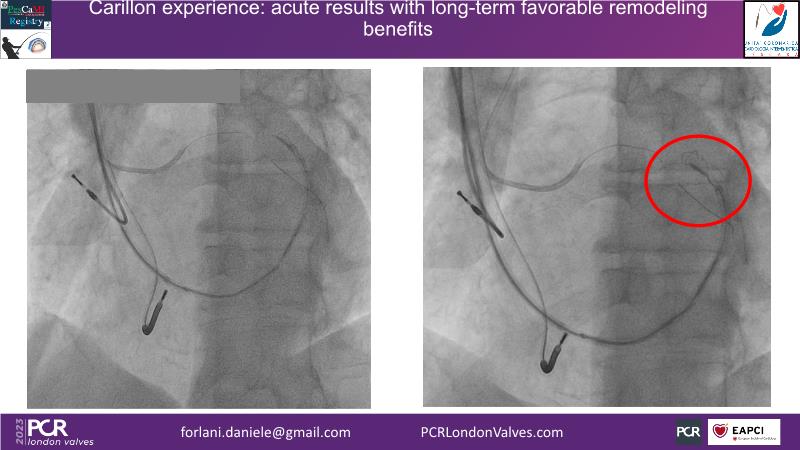

This session offers insights into combo therapy involving Carillon for patients with functional mitral regurgitation. It covers details of the EMPOWER trial, a double-blinded, sham-controlled study, and explores the potential benefits of early treatment for patients with functional mitral regurgitation.